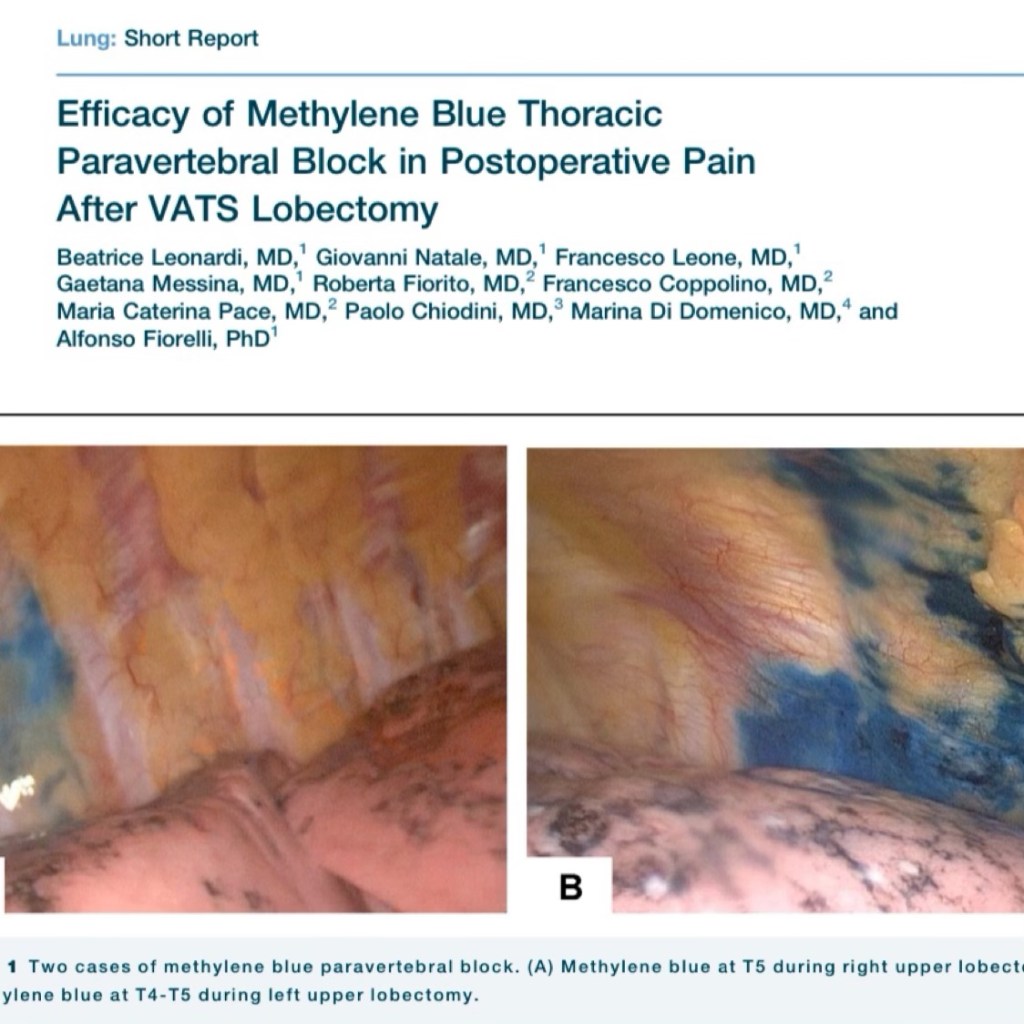

In questi casi una particolare tecnica chirurgia denominata “fissureless technique” che consiste nel sezionare la scissura dopo avere sezionato i vasi polmonari permette di eseguire intervento di lobectomia in toracoscopia. Nel caso in esame tale procedura è stata eseguita in un paziente di 83 affetto da carcinoma del polmone del lobo superiore. Eseguire l’ intervento secondo la tecnica tradizionale quale la toracotomia avrebbe aumentato il rischio di complicanze considerata la età e le patologie pre operatorie (pregressa ischemia cardiaca, BPCO e diabete). Pertanto si è deciso di procedere con la tecnica mini-invasiva della toracoscopia. La presenza di aderenze dovute alla pregressa pleurite e del tumore vicino ai vasi polmonari ed alla scissura ha reso la lobectomia particolarmente complessa. L’ intervento è stato eseguito con successo in toracoscopia andando a sezionare la scissura a fine intervento secondo la tecnica “fissureless”.

Il video mostra l’intervento e la particolare tecnica utilizzata.